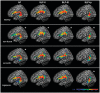

Primary progressive aphasia is a clinical syndrome that encompasses three major phenotypes: non-fluent/agrammatic, semantic and logopenic. These clinical entities have been associated with characteristic patterns of focal grey matter atrophy in left posterior frontoinsular, anterior temporal and left temporoparietal regions, respectively. Recently, network-level dysfunction has been hypothesized but research to date has focused largely on studying grey matter damage. The aim of this study was to assess the integrity of white matter tracts in the different primary progressive aphasia subtypes. We used diffusion tensor imaging in 48 individuals: nine non-fluent, nine semantic, nine logopenic and 21 age-matched controls. Probabilistic tractography was used to identify bilateral inferior longitudinal (anterior, middle, posterior) and uncinate fasciculi (referred to as the ventral pathway); and the superior longitudinal fasciculus segmented into its frontosupramarginal, frontoangular, frontotemporal and temporoparietal components, (referred to as the dorsal pathway). We compared the tracts' mean fractional anisotropy, axial, radial and mean diffusivities for each tract in the different diagnostic categories. The most prominent white matter changes were found in the dorsal pathways in non-fluent patients, in the two ventral pathways and the temporal components of the dorsal pathways in semantic variant, and in the temporoparietal component of the dorsal bundles in logopenic patients. Each of the primary progressive aphasia variants showed different patterns of diffusion tensor metrics alterations: non-fluent patients showed the greatest changes in fractional anisotropy and radial and mean diffusivities; semantic variant patients had severe changes in all metrics; and logopenic patients had the least white matter damage, mainly involving diffusivity, with fractional anisotropy altered only in the temporoparietal component of the dorsal pathway. This study demonstrates that both careful dissection of the main language tracts and consideration of all diffusion tensor metrics are necessary to characterize the white matter changes that occur in the variants of primary progressive aphasia. These results highlight the potential value of diffusion tensor imaging as a new tool in the multimodal diagnostic evaluation of primary progressive aphasia.